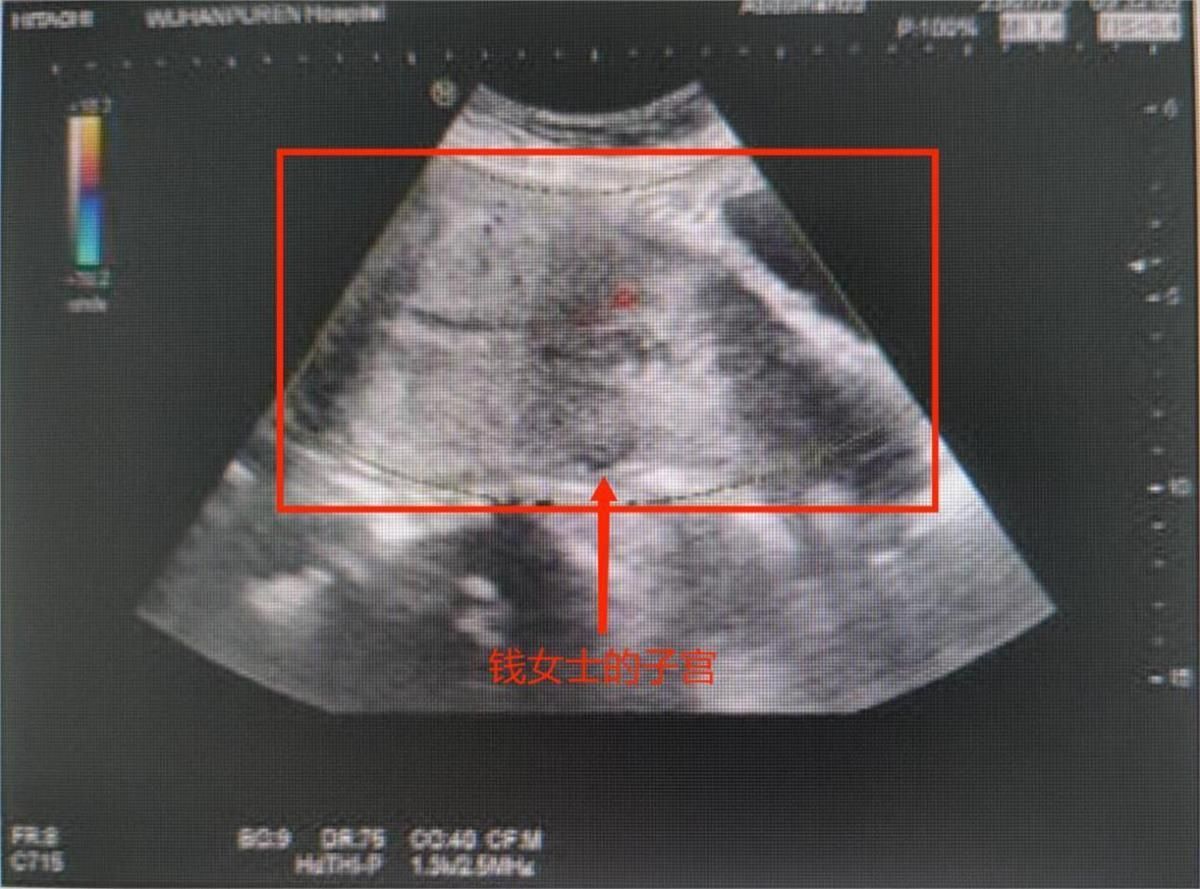

▲38歲女子誤將先兆流產當經期。(圖/翻攝自極目新聞)

由於錢女的宮腔內仍有殘留的胎盤尚未排出,武漢市普仁醫院產科醫生為錢女進行了無痛清宮手術,目前,錢女的恢復情況良好。